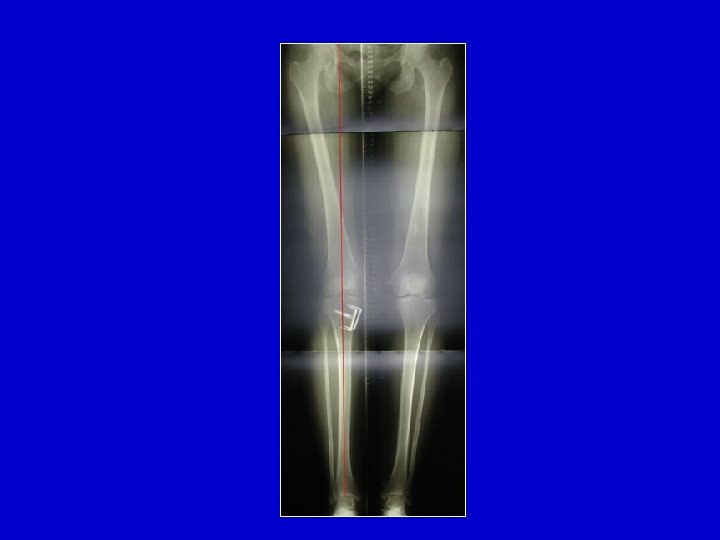

Necrosi del condilo femorale nell’adulto Aspetto all’inizio

L’evoluzione é sempre verso l’affossamento del condilo

Necrosi del condilo interno

La necrosi si accompagna in questo caso con l’artrosi del compartimento interno

Tentativo di trattamento con delle perforazioni di Pridie associate ad una osteotomia di scarico Adulto giovane